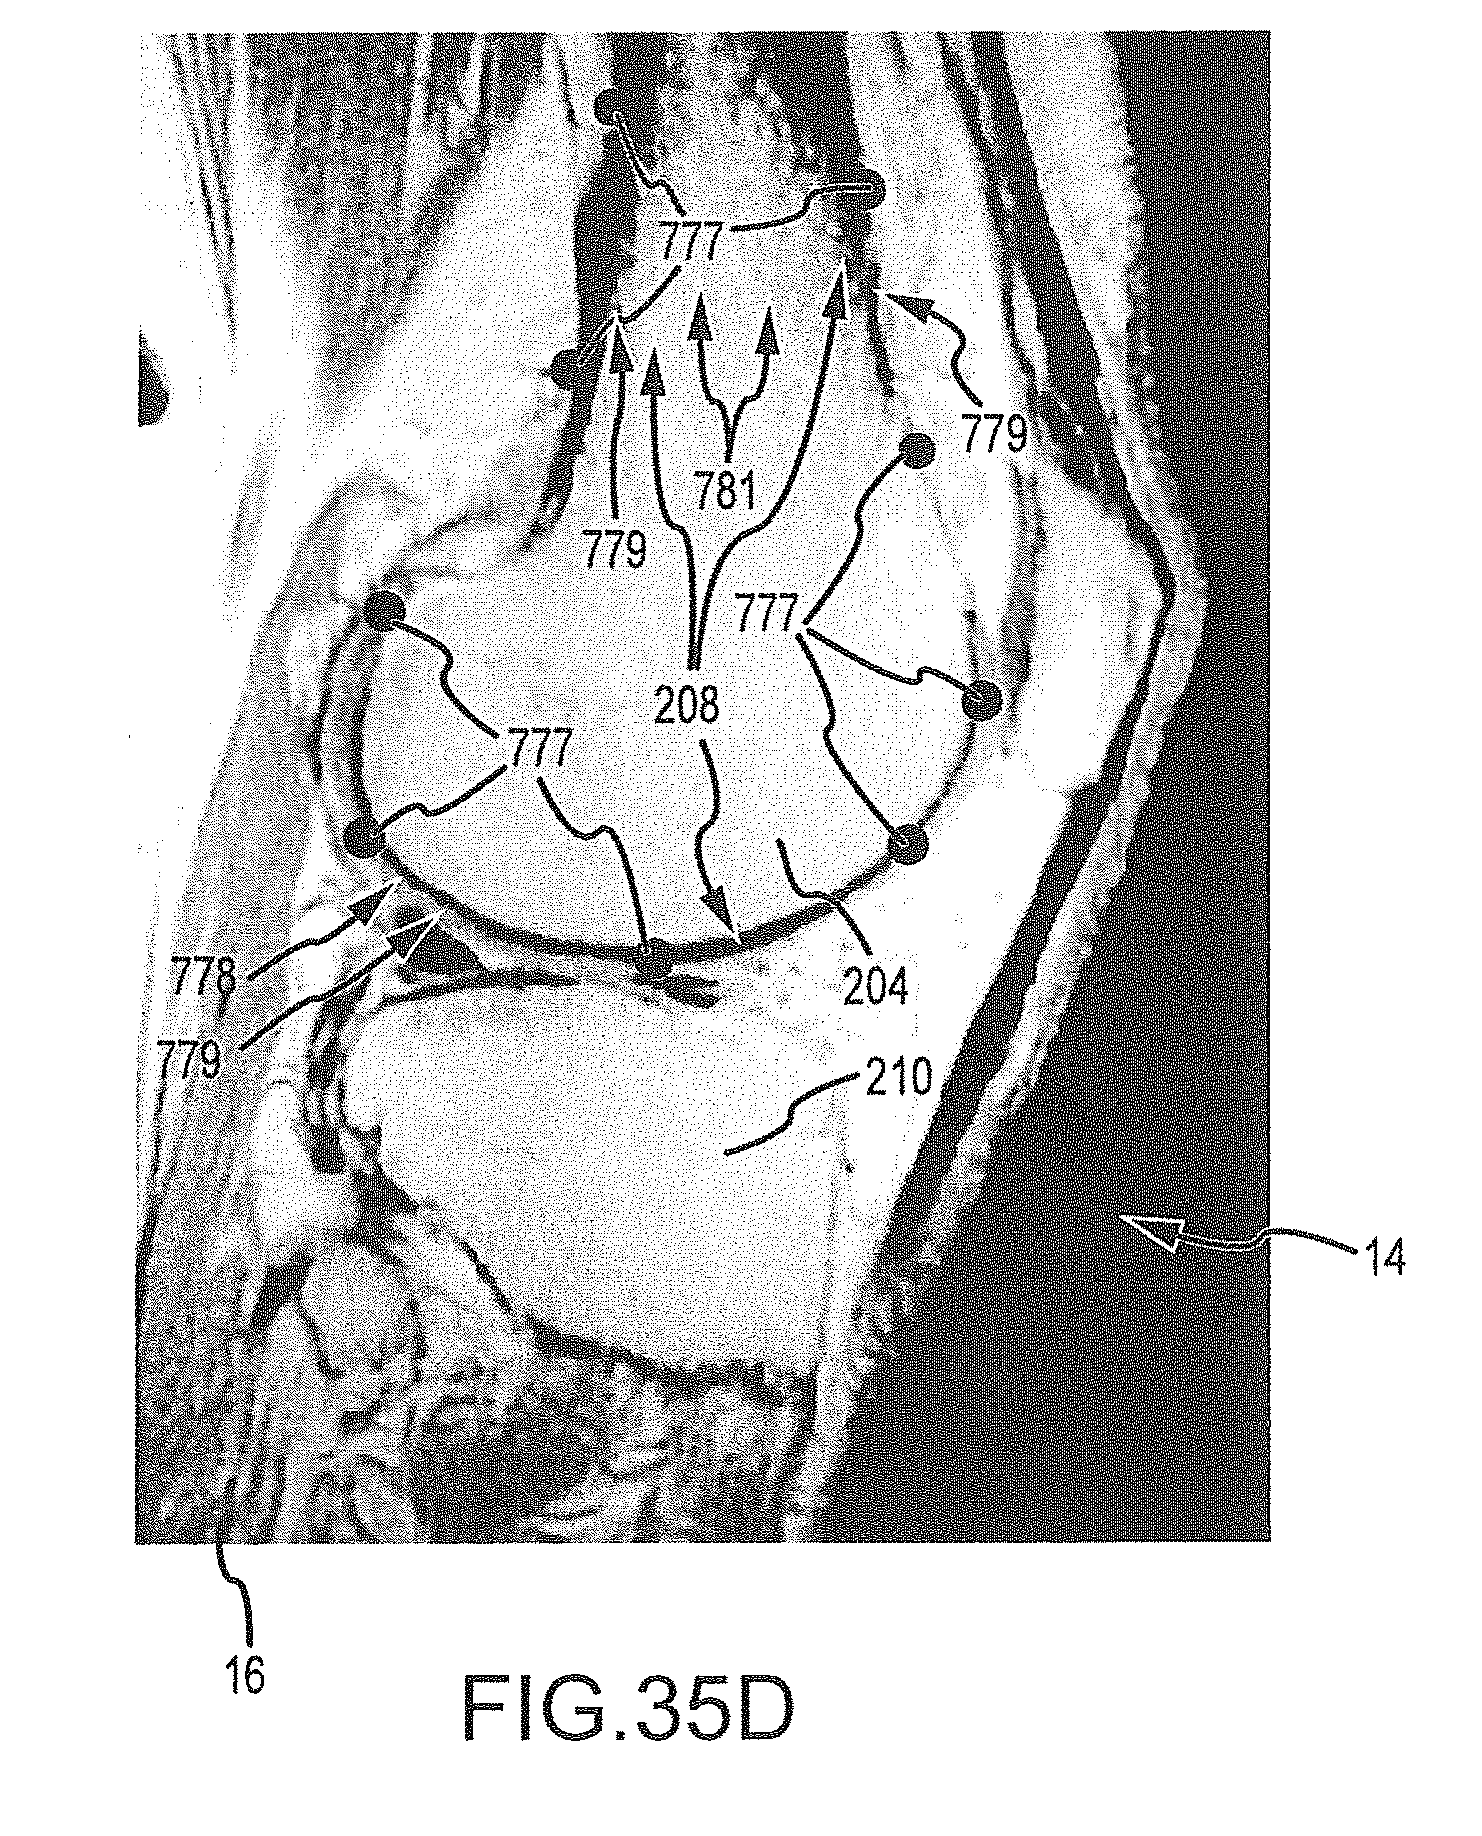

FIGS. 35A-35H are a series of sagittal image slices wherein landmarks have been placed according the process of FIG. 34.

[0095]

FIG. 37 is a flowchart illustrating the process of operation “Deform Golden Femur Mesh” of FIG. 36, the process including mapping the golden femur mesh into the target scan using registration techniques.

[0097]